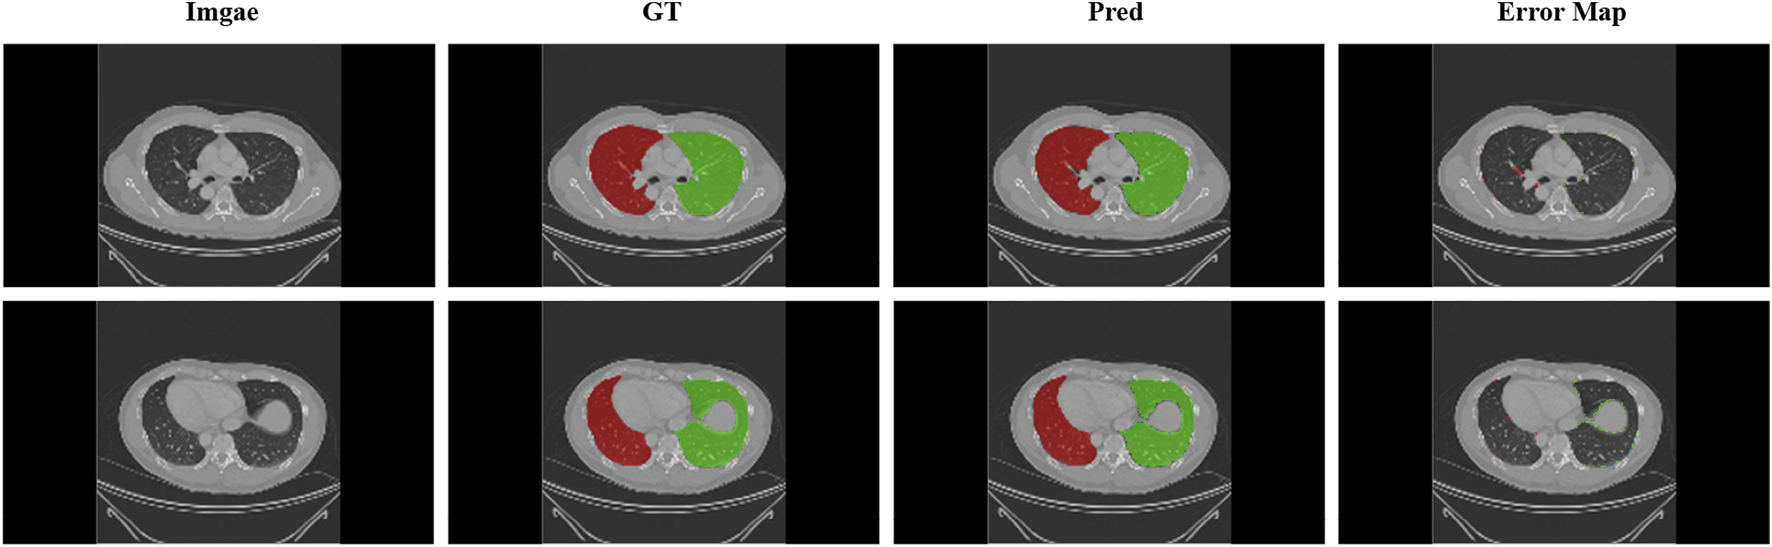

4.1 Left and right lung segmentation

In this paper, 3D-UNet is used to segment the left and right lungs of lung CT images in pre-processing. To avoid redundant areas being extracted due to incorrect segmentation, the maximum connected field of each channel is retained, reducing the false positive rate. The 148 cases of data were divided into 128 training cases and 20 test cases. Although the entire experiment included three networks and each network was trained independently, during the testing phase, the data from one patient was computed end-to-end. Therefore, to avoid data leakage between networks, the distribution of training and test data for the boundary generation and lobe segmentation networks was kept consistent with that of the lung parenchymal segmentation network. Dsc, Precision, Sensitivity (Se), Specificity (Sp) and Hausdorff distance (HD) will be used to evaluate that result of lung segmentation. The final test results are shown in Table 1. The results show that the most of the lung area is segmented and that the under and over-segmentation rates are low. Nevertheless, we have chosen to expand the bounding box by five pixels when we take it. Figure 3 shows the result of the segmentation and ground truth.

FIGURE 3. Display of lung segmentation results. Green areas: left lung; Red areas: right lung. Error map that performed the difference between the predicted and real results is shown.